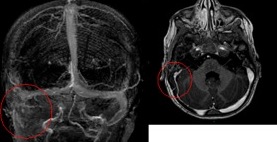

Al controllo clinico persisteva la tendenza alla retropulsione di lieve entità e la RM dell’encefalo dimostrava un’evoluzione in senso occlusivo dell’iniziale trombosi del seno sigmoideo, estesa anche al tratto distale del seno venoso trasverso (Figura 2).

Si decide pertanto di iniziare terapia con enoxaparina sottocute con successivo switch alla terapia anticoagulante orale con warfarin. La piccola è progressivamente migliorata dal punto di vista clinico, tollerando la terapia anticoagulante senza complicanze.